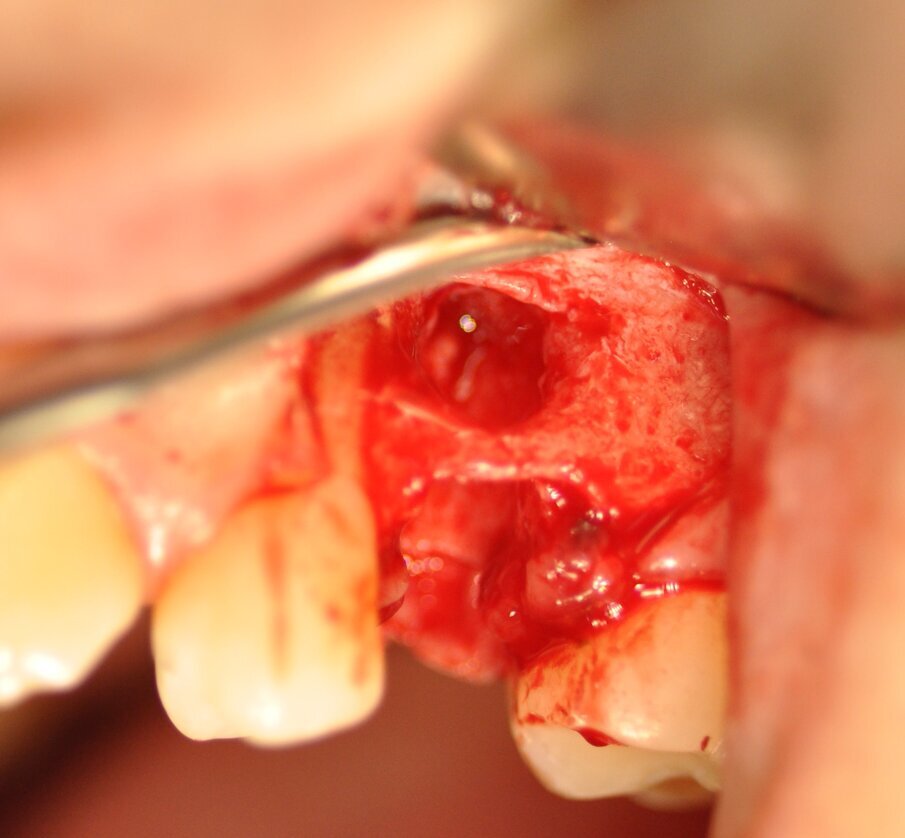

La paziente presentava un primo premolare superiore sinistro non recuperabile. La CBCT mostra la situazione iniziale (Fig. 1). Si noti quella che appare come una grande fenestrazione buccale nell’area della resezione radicolare (Fig. 2). Il dente fratturato è stato estratto (Figg. 3, 4). Lo scollamento del lembo di accesso rivela la fenestrazione buccale (Fig. 5). L’osteotomia è stata preparata secondo il protocollo di fresatura di Neoss ProActive Edge (Fig. 6). Successivamente viene posizionato un impianto Neoss ProActive Edge Ø 5.0 × 13 mm (Fig. 7). L’impianto è stato posizionato in una situazione di disponibilità ossea molto limitata e densità ossea media (Fig. 8). Nonostante le limitazioni dovute alla condizione ossea, è stata raggiunta una buona stabilità primaria. È stato utilizzato un torque di inserimento di 20 Ncm, l’ISQ è risultato in un range di 70/77. Per correggere la fenestrazione buccale è stato eseguito un innesto con particolato osseo di origine porcina (Fig. 9). L’innesto osseo è stato coperto con una membrana di collagene riassorbibile (Fig. 10). Il lembo mucoso è stato suturato attorno al pilastro di guarigione in PEEK, consentendo la guarigione in una sola fase (Fig. 11).